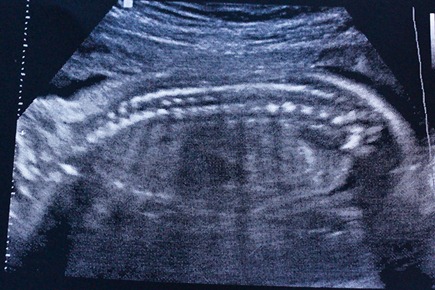

He’s healthy from head to toe. And he’s still a boy

The sardine shot! Nice [non-edible] spine : )